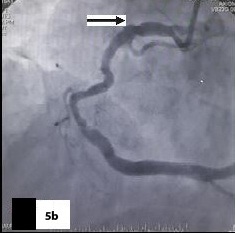

Five patients (12.5 %) had normal angiograms [Table/Fig-2,2b,3,3b], six (15%) had non-significant disease [Table/Fig-4,4b,5a,5b] and 29 patients (72.5%, 26 male & 3 female) had significant disease [Table/Fig-6a,6b],[7a,7band8] on CT coronary angiography, which was also proved on invasive angiography [Table/Fig-9]. The incidence of significant coronary detected was highest in age group of 41-60 years [Table/Fig-10].

Curved reformatted image with mixed palque

Catheter angiography image showing focal non-significant stenosis in RCA